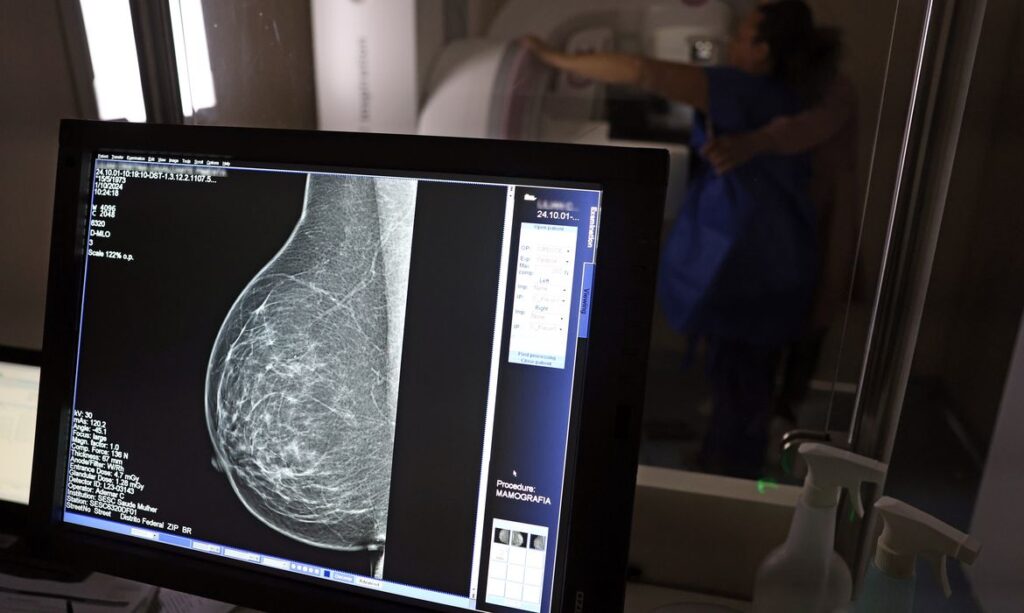

Nova lei garante folga para exames preventivos e obriga empresas a informar trabalhadores

<p><strong>Uma nova lei, <a href=publicada nesta segunda-feira (6), reforça o direito do trabalhador com contrato via Consolidação das Leis do Trabalho (CLT) de se afastar até três dias por ano para realizar exames preventivos de câncer, em desconto salarial.

O direito já estava incluído na CLT desde 2018. A partir de agora, as empresas passam a ser obrigadas a divulgar essa informação, além de outras relacionadas a campanhas oficiais de vacinação contra o HPV e sobre o acesso a serviços de diagnósticos de cânceres de mama, próstata e de colo do útero.

O texto estende o uso das folgas também para a realização de exames preventivos do HPV, além dos de câncer que já estavam previstos na legislação anterior. A a Lei 15.377 foi sancionada pelo presidente Luiz Inácio Lula da Silva, e publicada na edição do Diário Oficial da União (DOU).